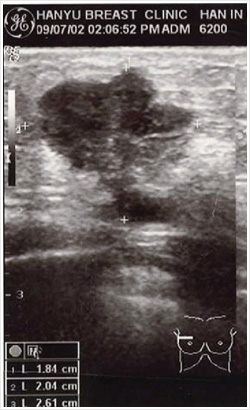

1. Before prayer - The result of sonogram (July 2, 2009) : The breast cancer tumor was 2.5 cm 2. After prayer - The result of sonogram (June 29, 2011): There is just the trace of breast cancer